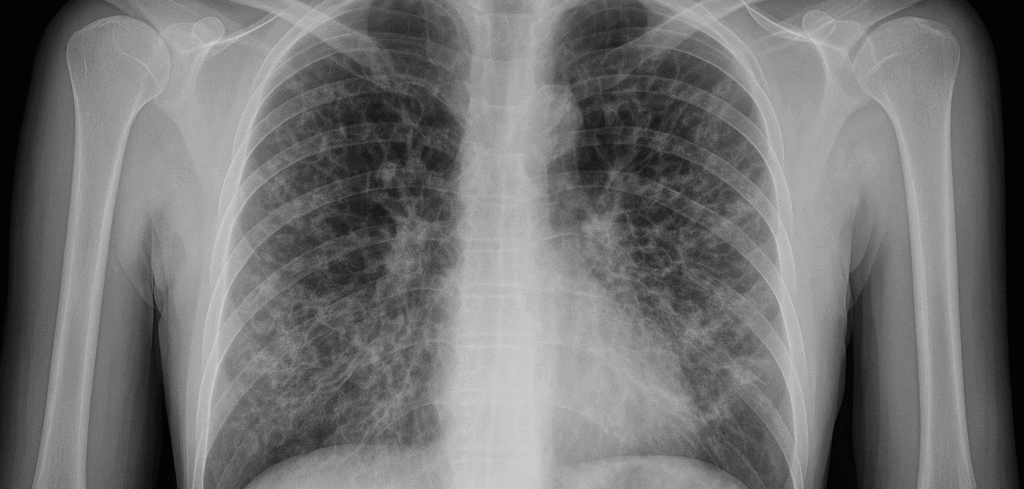

60代女性。肺マック症と気管支拡張症のご相談。

知人の紹介でお越しになられた方。呼吸器専門病院に通院中とのこと。咳と痰、のどの不快感、そして不安感が取れないとのことで相談に来られました。話を聞くと、肺マック症と気管支拡張症の治療を受けているが、医師は薬を死ぬまで続けないといけないと話したという。そのことが相当にショックで途方に暮れていたところ、当店で肺マック症が良くなったという話を聞いて飛んで来たとのことでした。肺マック症は、結核と並ぶ抗酸菌である非結核性抗酸菌のMAC菌による呼吸器感染症のことを言い、自然環境中の水系・土壌中、家畜などの動物、水道・貯水槽・浴槽などから菌を吸入することで感染するとされています。肺マック症の方には決まって感染症の反応穴に証が現れます。この方も糸錬功で確認したところ薬用人参と露蜂房(ロホウボウ)の証が確認できました。また咳と痰、のど、精神症状には半夏厚朴湯の証が見られました。肺マック症本体とそこから派生した様々な症状のほとんどは、恐らくこれらの薬で改善できると説明してしばらく飲んで頂きました。2週間後には咳と痰が改善しました。しかし、のどの不快感・不安感はまだ残ったままでしたが、このまま続けていれば治ると説明して続けてもらいました。半年後には自覚症状は全てなくなくなりました。笑顔で薬局に来られてレントゲン画像のことを話して帰られました。レントゲン画像の白いところは完全には消失していない状態でしたが自覚症状もないため良好とのことでした。糸錬功で確認すると、感染症の反応は殆ど治癒の状態であったため一旦服薬は中止として様子を見て頂きました。その後3か月間を経過観察としましたが再発することはなかったため当店での治療は終了としました。